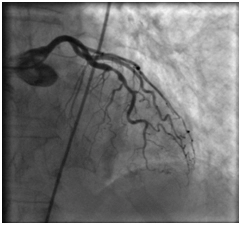

Ангиопластика и стентирование коронарных артерий

18.08.2011 интервенционным кардиохирургом в область стеноза проксимальной трети передней межжелудочковой артерии проведен баллонный катетер со стентом «Мульти-линк 8» размерами 3×12 мм, произведена имплантация.

В дистальную часть правой коронарной артерии проведен проводник 0,014". В область стеноза проведен баллонный катетер со стентом «Мульти-линк 8» размерами 3×12 мм, произведена имплантация.

На контрольных ангиограммах получен хороший кровоток